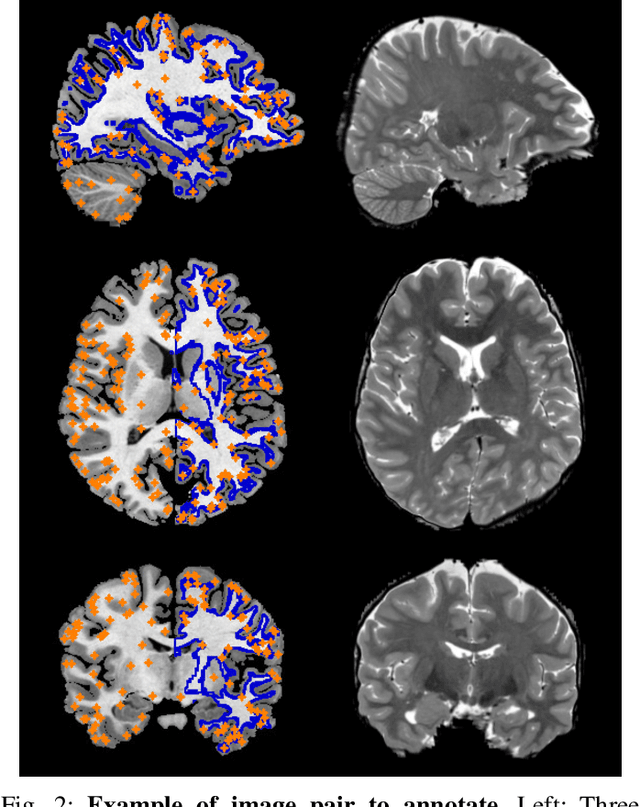

Abstract:Landmark correspondences are a widely used type of gold standard in image registration. However, the manual placement of corresponding points is subject to high inter-user variability in the chosen annotated locations and in the interpretation of visual ambiguities. In this paper, we introduce a principled strategy for the construction of a gold standard in deformable registration. Our framework: (i) iteratively suggests the most informative location to annotate next, taking into account its redundancy with previous annotations; (ii) extends traditional pointwise annotations by accounting for the spatial uncertainty of each annotation, which can either be directly specified by the user, or aggregated from pointwise annotations from multiple experts; and (iii) naturally provides a new strategy for the evaluation of deformable registration algorithms. Our approach is validated on four different registration tasks. The experimental results show the efficacy of suggesting annotations according to their informativeness, and an improved capacity to assess the quality of the outputs of registration algorithms. In addition, our approach yields, from sparse annotations only, a dense visualization of the errors made by a registration method. The source code of our approach supporting both 2D and 3D data is publicly available at https://github.com/LoicPeter/evaluation-deformable-registration.